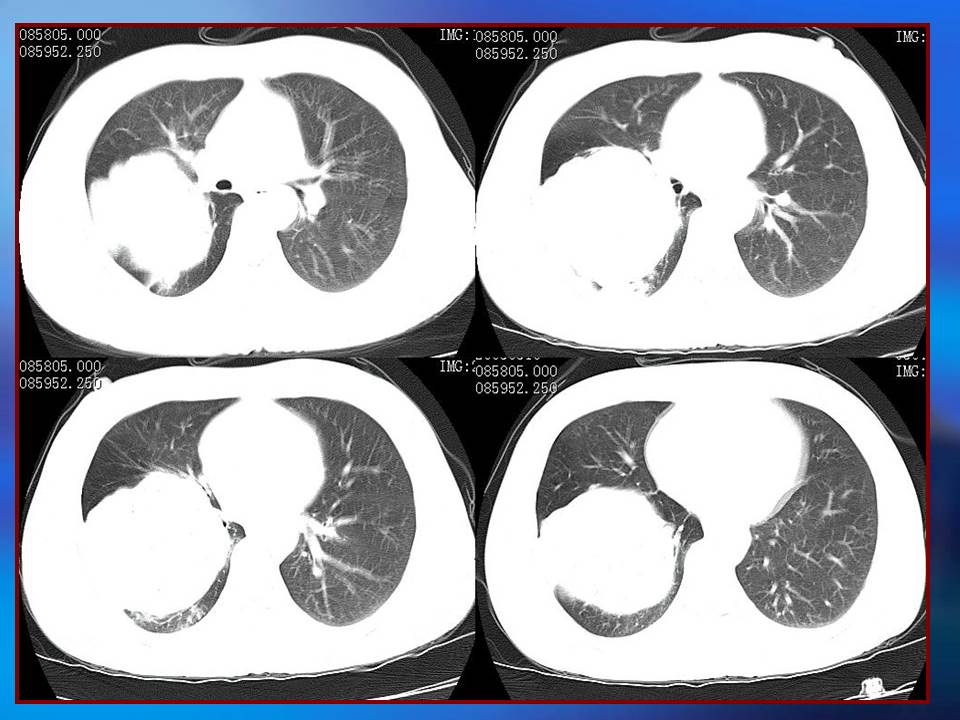

幻灯片1